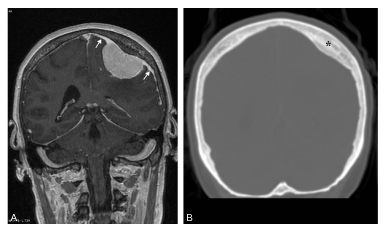

Fig. 61.2. Méningiome pariétal gauche.

Coupe frontale IRM pondérée en T1 avec injection de gadolinium (A) : masse pariétale gauche extraparenchymateuse (c’est-à-dire refoulant le cortex cérébral), prenant fortement le contraste, et associée à un épaississement méningé (flèches) avec hyperostose de la voûte crânienne au contact de la lésion (∗) sur le scanner en fenêtre osseuse (B).

Source : CERF, CNEBMN, 2022.